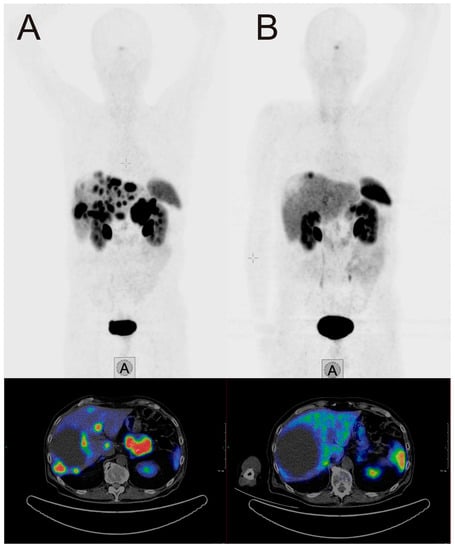

The β-emitter-labeled somatostatin analogue, 177Lu-DOTA-D-Phe-Tyr3-octreotate (DOTATATE), improves PFS, quality of live, and presumably OS. In the NETTER-1 trial, 229 patients with progressive, well-differentiated (G1 or G2) neuroendocrine tumors were randomized to be treated either with 60 mg long-acting octreotide LAR or 177Lu-DOTATATE and 30 mg octreotide LAR [20]. After 20 months, PFS was 62% in the group treated with 177Lu-DOTATATE and 30 mg Octreotide LAR compared with 11% in the Octreotide LAR group. This difference was statistically significant. The response rate was 18% in the group with radionuclide treatment vs. 3% in the group treated with Octreotide LAR. Interestingly, OS was higher in the radionuclide group too, as only 14 deaths occurred in the 177Lu-DOTATATE group compared to 26 in the Octreotide LAR monotherapy group. Radionuclide therapy did not cause increased rates of nephrotoxicity, however, the rate for grade 3 or 4 neutropenia, thrombocytopenia, and lymphopenia was 1%, 2%, and 9% respectively. Octreotide LAR (60 mg/d) monotherapy in contrast was not hematotoxic. In an additional analysis of the NETTER trial data, a higher quality of life was found in patients treated with 177Lu-DOTATATE compared to octreotide LAR monotherapy [21]. An image example of a patient with very good treatment response to 177Lu-DOTATATE is shown in Figure 1. The second example demonstrates a full response achieved with 177Lu-DOTATATE treatment. In Figure 2, images of a patient with pancreatic NETs during four cycles of treatment with a total dose of 28.8 GBq 177Lu-DOTATATE are presented. After the last cycle, no active tumor tissue was found in PET/CT imaging, and also in the follow-up after 6 and 12 months, no tumor localization could be identified, corresponding to a full response.

Figure 1. Example of a 70-year-old male patient with a pancreatic neuroendocrine tumor (NET), first diagnosed in April 2017, with an initial ki-67 index of 3%. After initial treatment with everolimus, liver metastases showed progress in November 2017. (A) SSTR-PET/CT at this time point. The patient was treated with four cycles 177Lu-DOTATATE (total dosage 29.3 GBq) between November 2017 and July 2018. Two months after the last cycle, SSTR-PET/CT (B) showed a very good response. Chromogranin dropped in the same interval from 1004 µg/L to 140 µg/L.